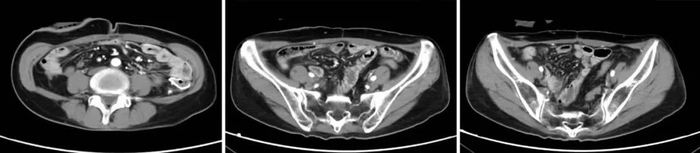

该患者在4年前经穿刺活检确诊恶性腹膜间皮瘤,经系统性全身治疗后病情仍进展,出现乏力、恶心、呕吐、腹痛等症状,检查提示广泛腹膜病变,大网膜病变尤其明显,呈大饼状覆盖在胃肠道表面,合并血性腹水。患者全身状况较差,存在营养不良、贫血、水电解质紊乱、感染等情况。为了更好地控制病情,患者在对症支持治疗的基础上,接受了经动脉导管灌注化疗联合载药微球栓塞治疗(D-TACE)、腹腔热灌注综合治疗及靶向药物治疗。经上述治疗后,患者肿瘤负荷明显减小,病情逐渐好转,稳定后采用抗血管生成药物、中成药维持治疗。为了进一步控制病情,患者于今年4月接受了肿瘤细胞减灭术治疗,术后采用相关治疗,目前恢复良好。